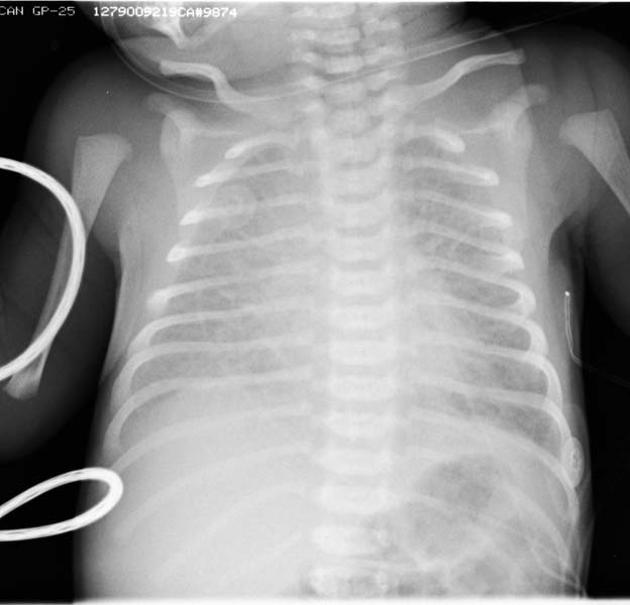

ΠΡΠΎ ΡΠΎΡΡΠΎΡΠ½ΠΈΠ΅ ΠΌΠΎΠΆΠ½ΠΎ ΠΎΠ±Π½Π°ΡΡΠΆΠΈΡΡ Ρ ΠΏΠΎΠΌΠΎΡΡΡ ΡΠ΅Π½ΡΠ³Π΅Π½ΠΎΠ³ΡΠ°ΡΠΈΠΈ ΠΈΠ»ΠΈ ΠΈΠ½ΠΎΠ³Π΄Π° Ρ ΠΏΠΎΠΌΠΎΡΡΡ Π£ΠΠ Π΄ΠΎ ΡΠΎΠΆΠ΄Π΅Π½ΠΈΡ. Π ΡΡΠΆΠ΅Π»ΡΡ ΡΠ»ΡΡΠ°ΡΡ ΠΌΠΎΠΆΠ΅Ρ ΠΏΠΎΡΡΠ΅Π±ΠΎΠ²Π°ΡΡΡΡ Ρ ΠΈΡΡΡΠ³ΠΈΡΠ΅ΡΠΊΠΎΠ΅ Π²ΠΌΠ΅ΡΠ°ΡΠ΅Π»ΡΡΡΠ²ΠΎ, Ρ ΠΎΡΡ ΠΎΠ±ΡΡΠ½Π°Ρ ΠΊΠ»ΠΈΠ·ΠΌΠ° ΡΠ²Π»ΡΠ΅ΡΡΡ ΠΏΠ΅ΡΠ²ΡΠΌ Π²Π°ΡΠΈΠ°Π½ΡΠΎΠΌ, ΠΊΠΎΡΠΎΡΡΠΉ ΠΈΡΠΏΠΎΠ»ΡΠ·ΡΠ΅ΡΡΡ Π² Π΄Π΅ΡΡΠΊΠΈΡ Π±ΠΎΠ»ΡΠ½ΠΈΡΠ°Ρ . ΠΡΠ»ΠΈ Ρ ΡΠ΅Π±Π΅Π½ΠΊΠ° Π±ΡΠ΄Π΅Ρ ΠΎΠ±Π½Π°ΡΡΠΆΠ΅Π½ΠΎ ΡΡΠΎ Π·Π°Π±ΠΎΠ»Π΅Π²Π°Π½ΠΈΠ΅, Π΅Π΅ ΡΠ°ΠΊΠΆΠ΅ ΠΏΡΠΎΠ²Π΅ΡΡΡ Π½Π° ΠΌΡΠΊΠΎΠ²ΠΈΡΡΠΈΠ΄ΠΎΠ·.